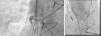

Case BA 70-year-old female with a history of CAD and previous CABG (LIMA-LAD, SVG-OM), peripheral vascular disease, diabetes, hypertension, and hyperlipidemia was admitted eight months after CABG with an acute non-ST-elevation myocardial infarction (NSTEMI), with troponin I of 8 ng/ml (normal: 0.0-0.04). Cardiac catheterization revealed significant native LAD and left circumflex (LCx) disease. The LIMA-LAD graft was patent, and since an extensive search including aortography revealed no other patent grafts (Figure 2A), it was assumed that the SVG-OM was occluded. Consequently, percutaneous transluminal balloon angioplasty and stenting of the native LCx/OM was performed.

Seven months later, she was readmitted with angina and a positive nuclear stress test suggestive of inferolateral ischemia. Repeat cardiac catheterization this time using an AL1 catheter showed a widely patent SVG-OM graft with good distal runoff (Figure 2B). Medical therapy was optimized. It was concluded that the SVG-OM was missed during the previous cardiac catheterization, possibly leading to unnecessary intervention on the native LCx. This could have potentially led to competitive flow and subsequent closure of a patent graft.

Case CA 52-year-old male had a history of CAD and previous CABG (LIMA-LAD, SVG-PDA, SVG-OM). On admission for NSTEMI, cardiac catheterization revealed a patent LIMA-LAD, an occluded SVG-OM, and 90% stenosis of the SVG-PDA, for which he received a stent.

Two years later, he presented with another NSTEMI (troponin I 8.5 ng/ml [normal: 0.0-0.04]). This time the SVG-PDA was considered totally occluded and optimized medical management was offered. On another admission for NSTEMI and worsening LV dysfunction, his ejection fraction dropped from 45% to 20%, and another cardiac catheterization showed that the SVG-PDA was not totally occluded as assumed previously, but was rather 99% stenosed ostially (Figure 2C). Selective engagement was achieved using a multipurpose catheter with gentle manipulation followed by angioplasty and successful stent placement, with restoration of TIMI 3 flow (Figure 2D). In this case, we can speculate that a timely intervention on this lesion could have avoided the drop in left ventricular function.